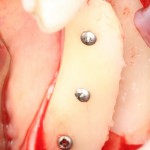

Остеопластика — всего одна операция.